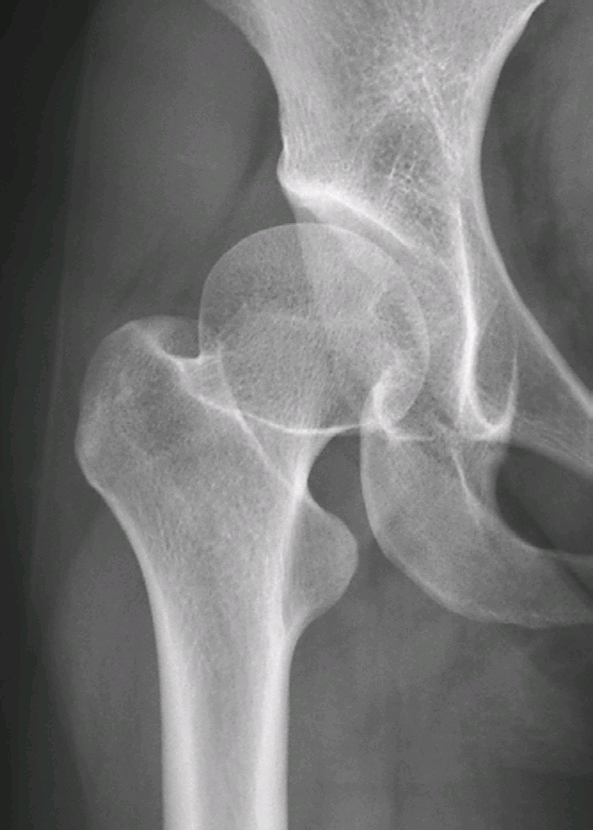

右侧髋臼发育不良

右髋正位片,示右侧髋臼变浅,Sharp角增大,髋臼覆盖率降低,CE角变小